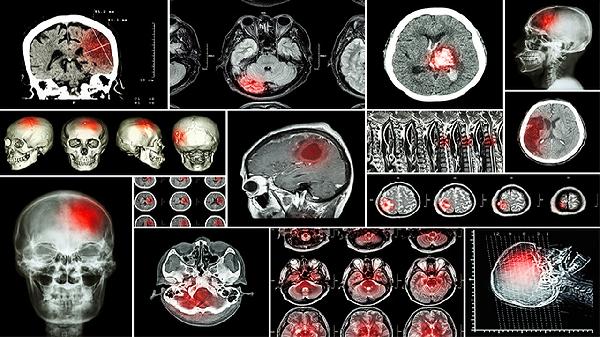

受伤后72小时内需复查评估恢复情况。后续每两周进行神经系统检查。通过平衡测试、反应力测试监测认知功能。必要时进行CT或MRI影像学复查。医生会根据恢复进度调整康复方案。